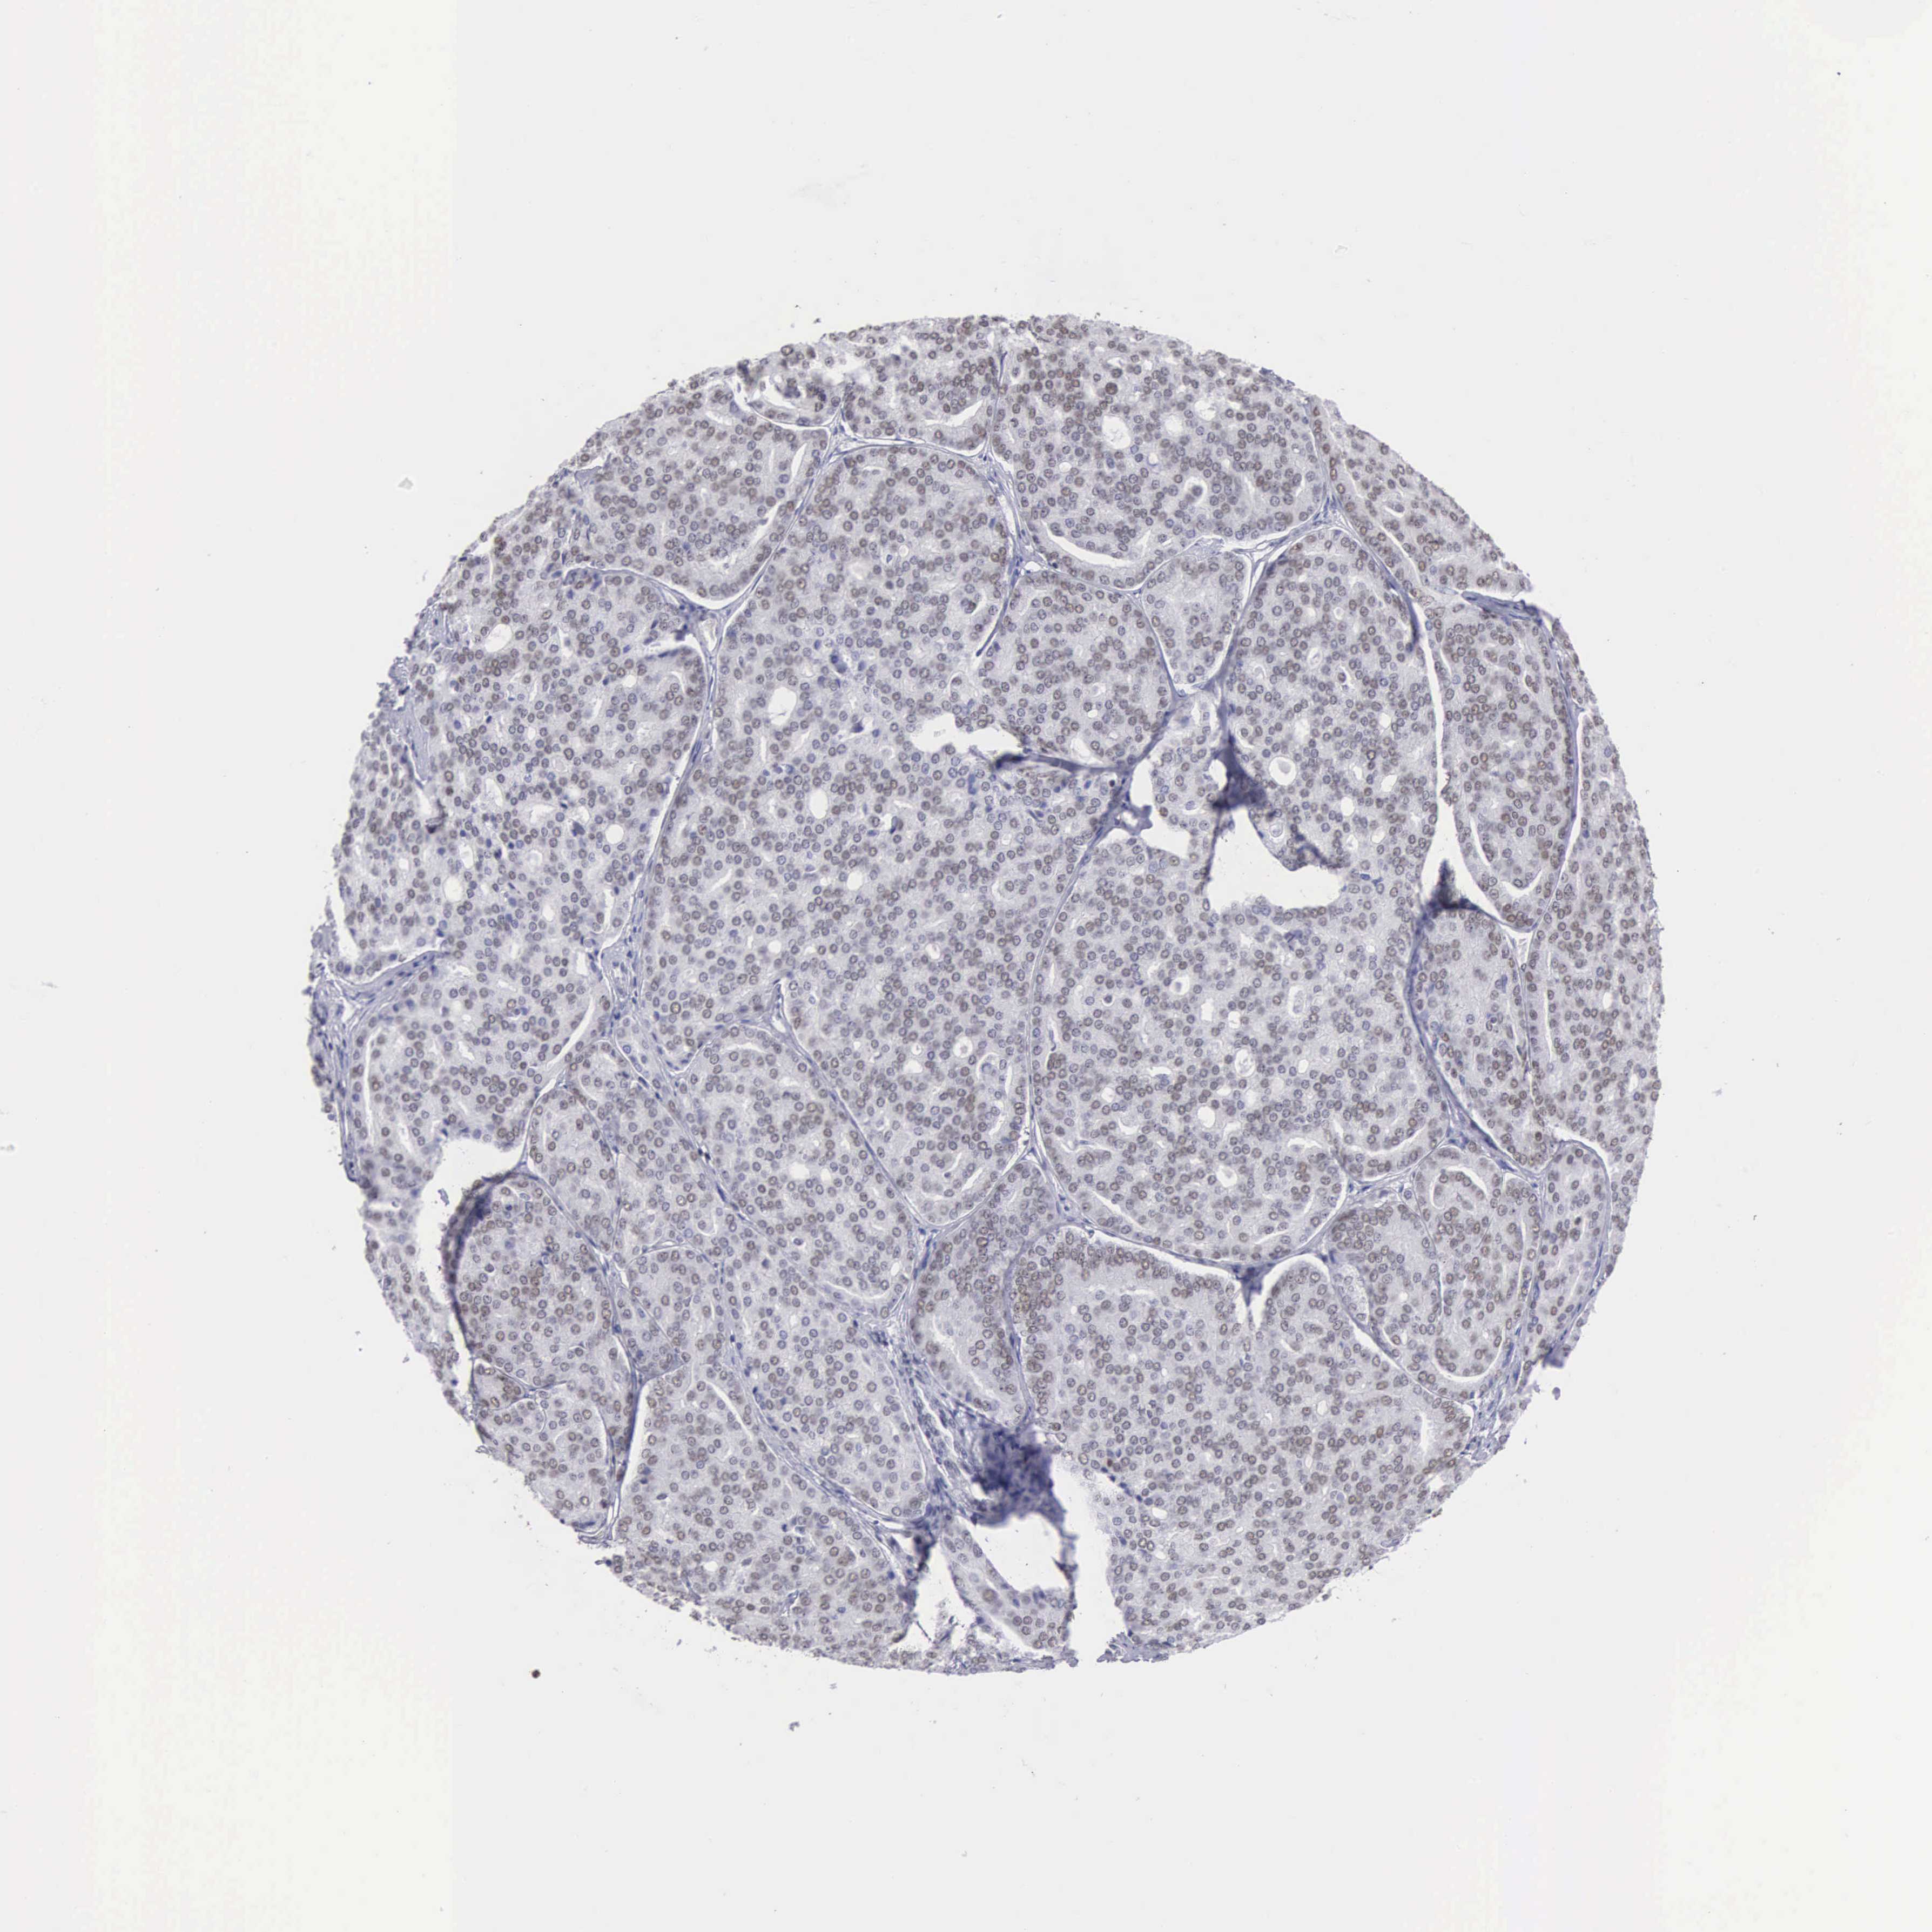

PROSTATE CANCER - Protein expressioni

A mouse-over function shows sample information and annotation data. Click on an image to view it in a full screen mode. Samples can be filtered based on level of antibody staining by selecting one or several of the following categories: high, medium, low and not detected. The assay and annotation is described here.

Antibody stainingi

Antibody staining in the annotated cell types in the current human tissue is reported as not detected, low, medium, or high, based on conventional immunohistochemistry profiling in selected tissues. This score is based on the combination of the staining intensity and fraction of stained cells.

Each image is clickable and will lead to virtual microscopy that enables deeper exploration of all samples and also displays staining intensity scores, fraction scores and subcellular localization as well as patient and tissue information for each sample.

Antibody HPA000427

Antibody CAB004680

Staining

High

Medium

Low

Not detected

Intensity

Strong

Moderate

Weak

Negative

Quantity

>75%

75%-25%

<25%

None

Location

Nuclear

Cytoplasmic/membranous

Cytoplasmic/membranous,nuclear

Adenocarcinoma, Medium grade

Adenocarcinoma, Low grade

Adenocarcinoma, High grade